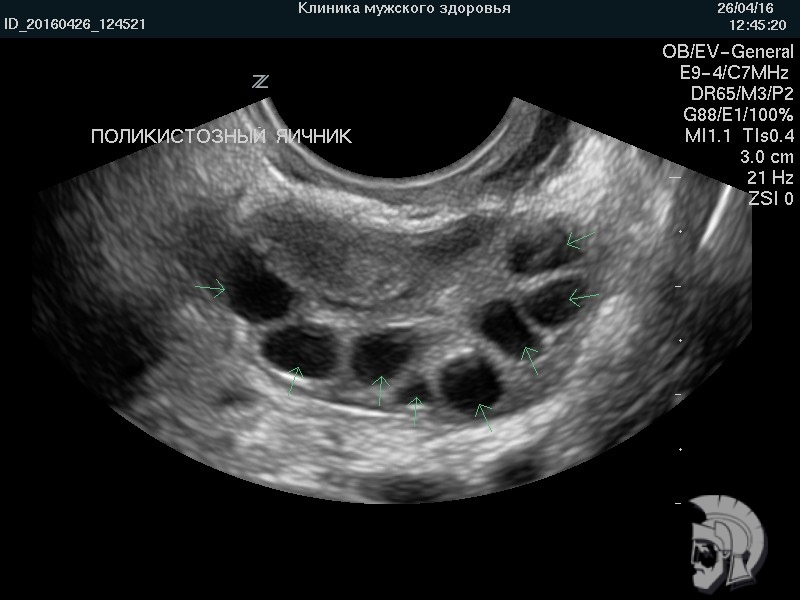

| Фото поликистозного яичника. Множественные мелкие фолликулы («кисты») указаны стрелками |